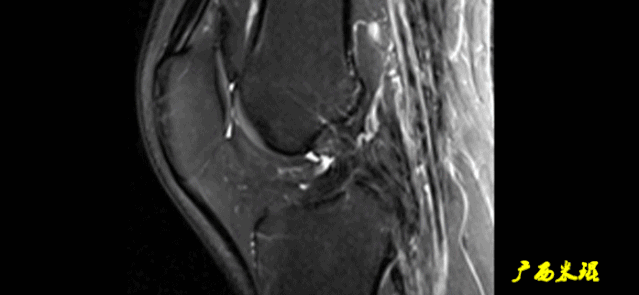

5)撕脱骨折:

一般为ACL胫骨附着部的撕脱。

韧带完整,信号多正常。

6)假瘤:

韧带损伤后断端较整齐,残端组织增生并被滑膜包裹呈“瘤状”,如果突出于前方为“独眼征”。

多见于韧带股骨附着部撕裂及部分撕裂。

7)扭曲和空虚:

髁间窝内似隐隐约约有低信号,边缘明显,中央空虚;或者中央有低信号,但扭曲如麻花状。

多为陈旧损伤,仅存ACL的滑膜,里面可有少量的韧带纤维,粘附在后方,随着膝关节的长时间屈伸逐渐呈扭曲状。